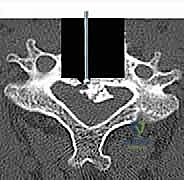

الخطوة 5: التثبيت بالشريحة والمسامير

لضمان ثبات الدعامة ومنع حركتها حتى يكتمل الالتحام العظمي (الذي يستغرق عدة أشهر)، يتم تثبيت شريحة معدنية من التيتانيوم على الجزء الأمامي من الفقرات السليمة (التي تقع أعلى وأسفل الدعامة) باستخدام مسامير طبية خاصة.